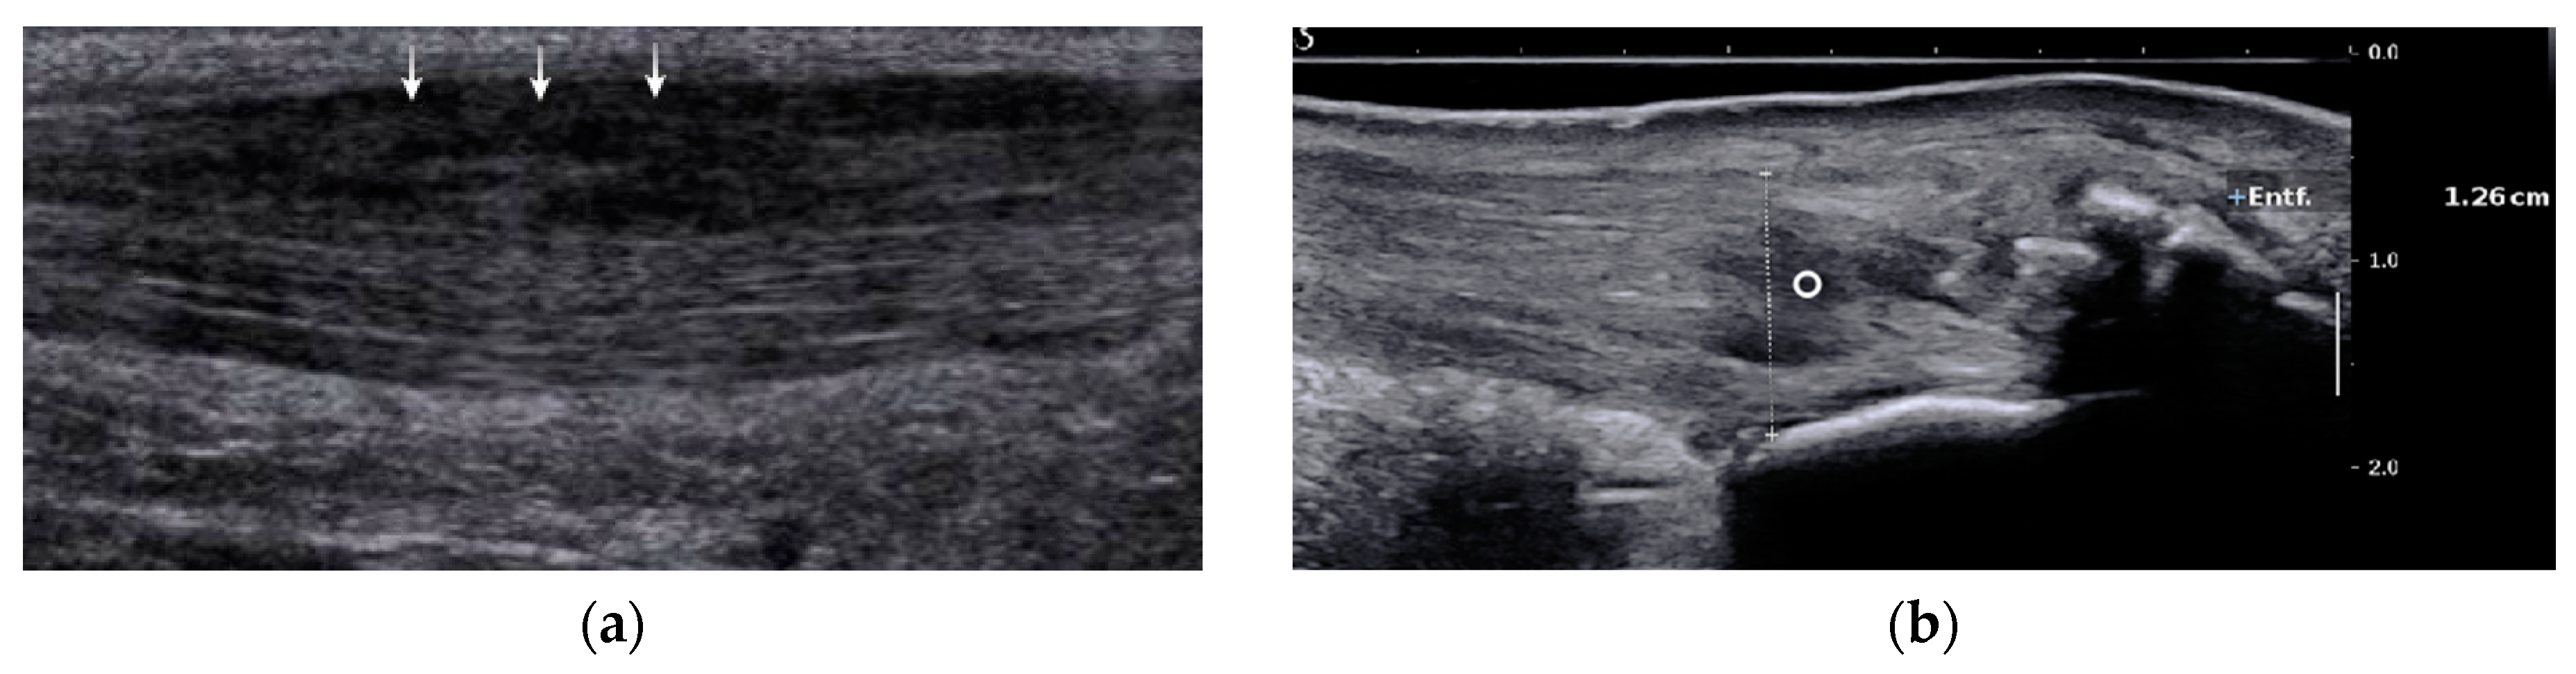

The majority of studies report that with ultrasound it is difficult to distinguish partial ruptures from focal degenerative changes, since partial ruptures appear with a wavy, irregular echo pattern with accompanying focal hypoechogenic areas, detectable neovascularization, and tendon thickening that are also findings in Achilles tendinopathy [19,23,26,28,29]. A more specific finding might be a disrupted dorsal Achilles tendon border [19,28] (Figure 2a). The detection of proximal partial ruptures close to the myotendinous junction and the differentiation between older partial ruptures and intratendinous tendinopathy are challenging with ultrasound [28,30] (Figure 2b). In MRI, a partial tear is defined as tendon thickening with a hyperintense signal on T1 and a strong hyperintense signal on magnetic resonance (MR) images with fluid-sensitive (T2-weighted and inversion recovery) sequences [29,30,31] (Figure 3). Typically, signal intensity is analogous to free fluid. A hyperintense area directly located at the tendon border should be interpreted as a partial rupture [30]. Due to muscle inactivity, isolated fatty degeneration and edema in the calf muscles might represent a subsequent state of a partial or total rupture [31]. The sensitivity of MRI in detecting partial tears is high (positive predictive value 0.94, n = 18), but studies directly comparing the accuracy of MRI and ultrasound are rare [32]. In a prospective study of Kayser et al., only one-fifth of partial lesions were noticed with B-Mode ultrasound whereas MRI detected five-fifths of partial ruptures [24].

Figure 2. US images of partial Achilles tendon ruptures: (a) partial rupture in the dorsal part of the Achilles tendon midportion (arrows); (b) partial rupture in insertional area of the Achilles tendon (circle). US; ultrasound.